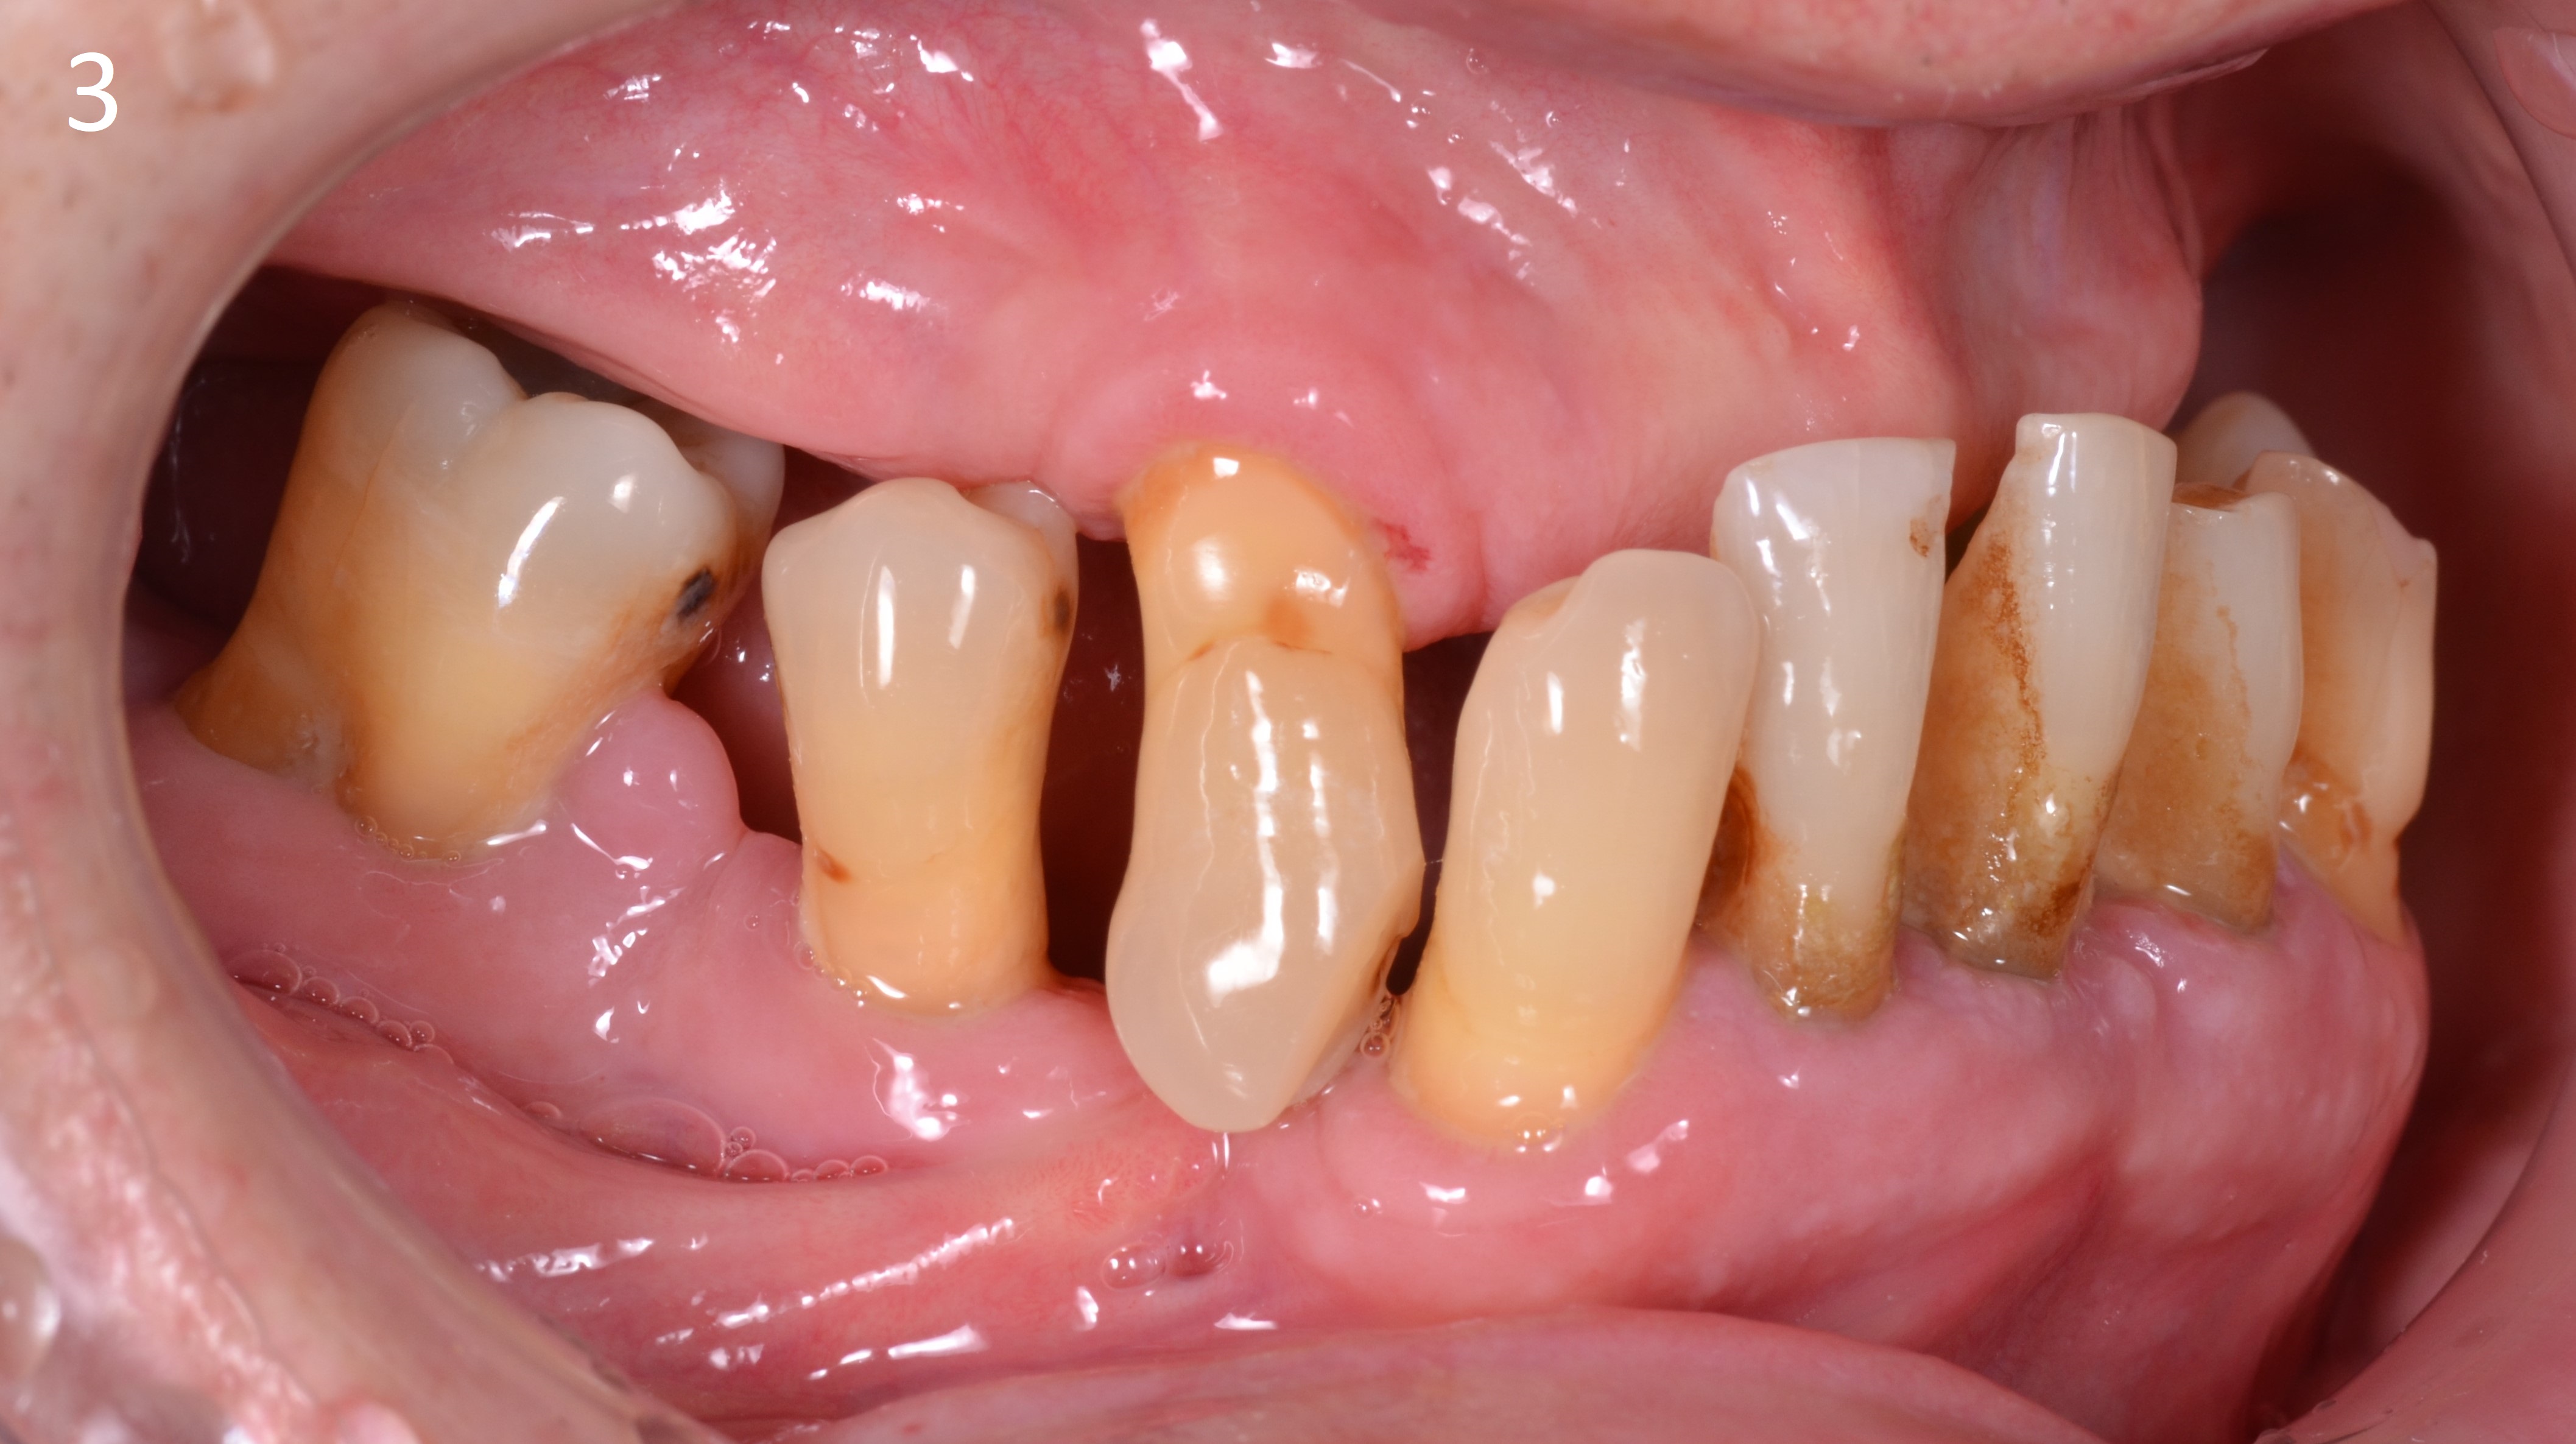

Пациент 65 лет обратился за комплексной стоматологической реабилитацией с жалобами на отсутствие зубов и эстетическую неудовлетворенность.

Пациент долгое время не обращался за стоматологической помощью, вследствие чего были утеряны зубы на верхней и нижней челюсти.

В полости рта наблюдаются пародонтальных патологии имеющихся зубов, зубоальвеолярное изменение в виде феномена Попова – Годона (рис 1,2,3.)